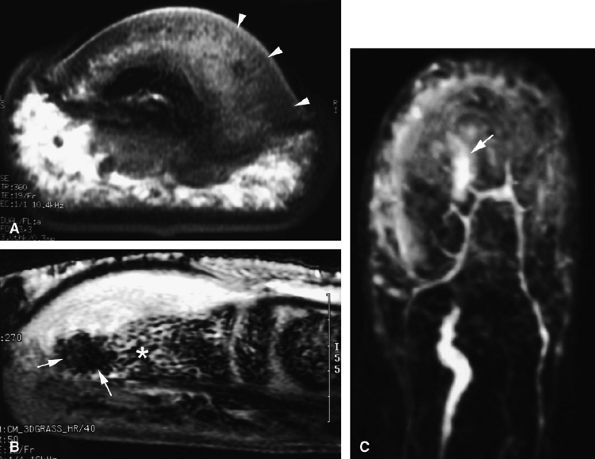

FIGURE 11.80 ● Arteriovenous malformation. (A) Axial T1-weighted image, (B) coronal post-contrast fat-suppressed T1-weighted image, and (C) MR angiogram showing a high-velocity vascular malformation of the hypothenar eminence with flow void artifacts (arrows). The angioarchitecture is better assessed with MR angiography.

Nodular or tubular enhancement may be seen after gadolinium administration. MRA is complementary to standard MR studies, providing precise details of the angiographic appearance of the malformation (Fig. 11.78). MRA of the fingers is technically challenging because of the small caliber of blood vessels and their changing orientation. The MRA technique that is most suited to the fingers is a 3D coronal acquisition after gadolinium administration. This rapid technique (requiring less than 30 seconds for acquisition) yields high spatial resolution and is not dependent on vessel orientation. Injection of a gadolinium test dose allows precise determination of maximum arterial enhancement.180 Temporal resolution remains inferior to DSA.4

better angiographic assessment of the venous malformation than arteriography alone.116